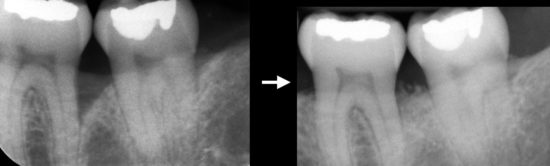

Dans les cas plus sévères de maladies parodontales, il peut rester des défauts osseux adjacent aux dents. Une approche régénérative est favorisée en guise de traitement, dans la mesure du possible. La régénération tissulaire guidée (RTG) fait appel à l’utilisation de techniques et de matériaux de pointe pour recréer une partie du tissu osseux perdu en raison de la maladie parodontale.

Radiographies démontrant la régénération de l’os adjacent à la racine de la dent